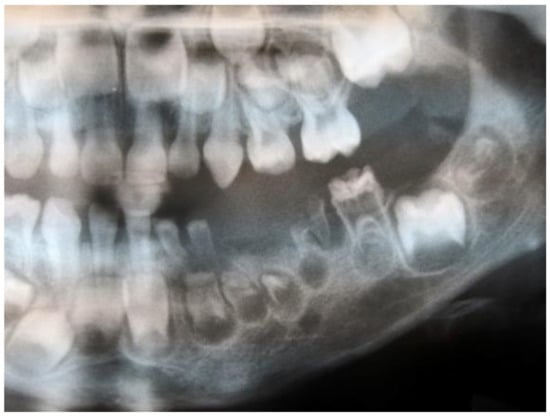

| Radiological features | All n= 166 | Male n= 79 | Female n= 87 | p-Value |

| ghost teeth | 100 | 100 | 100 | - |

| poorly developed buds | 92.2 | 91.1 | 93.1 | 0.638 |

| periapical lesions | 39.2 | 40.5 | 37.9 | 0.734 |